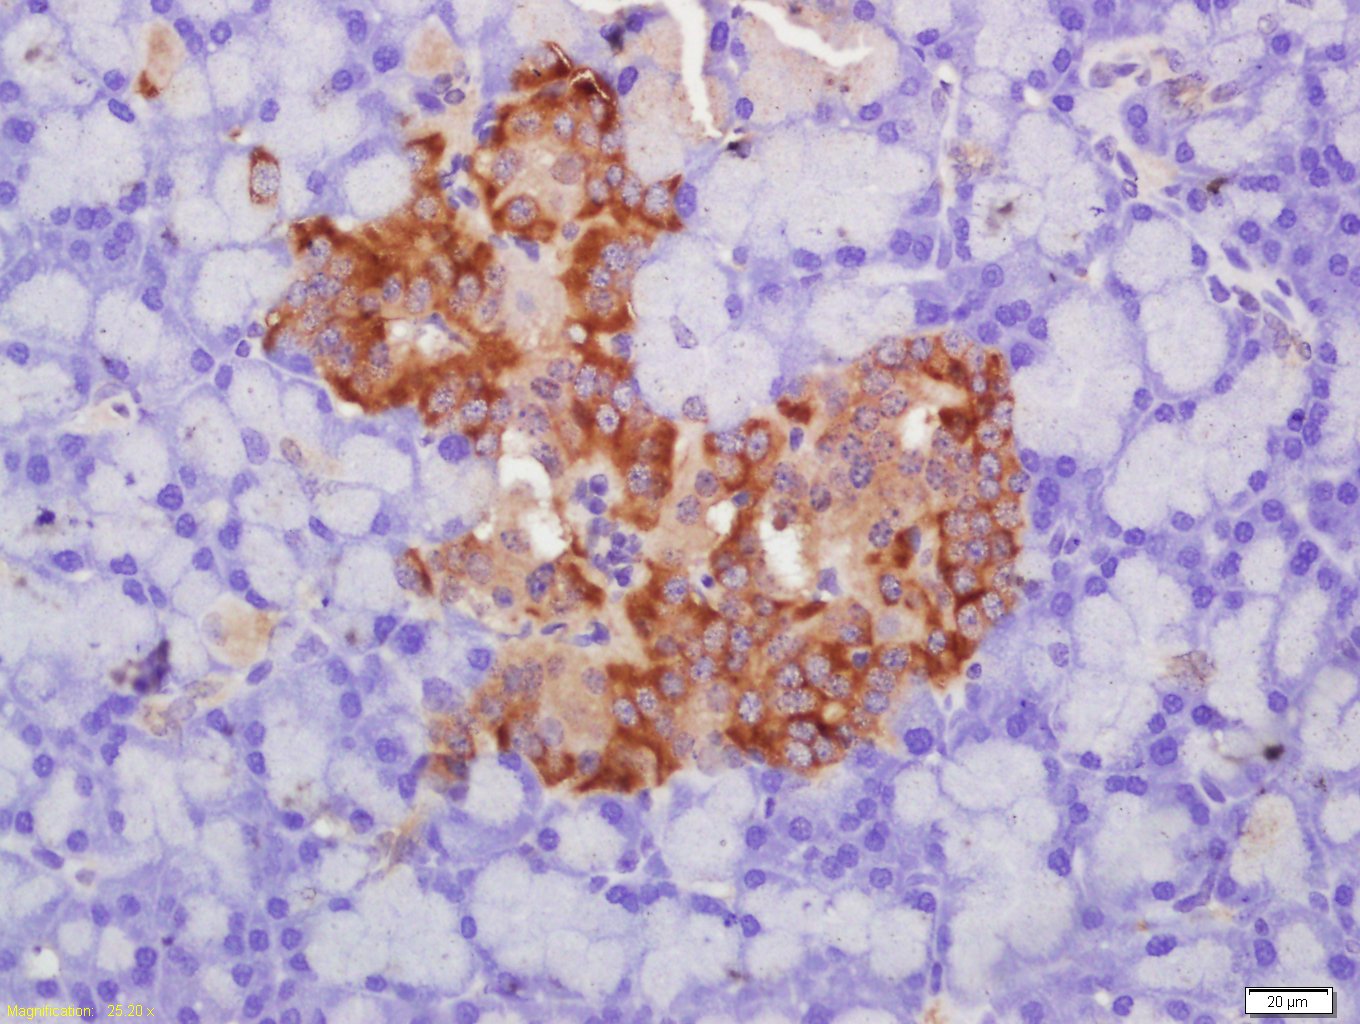

Paraformaldehyde-fixed, paraffin embedded (rat pancreas tissue); Antigen retrieval by boiling in sodium citrate buffer (pH6.0) for 15min; Block endogenous peroxidase by 3% hydrogen peroxide for 20 minutes; Blocking buffer (normal goat serum) at 37°C for 30min; Antibody incubation with (Glut2) Polyclonal Antibody, Unconjugated (bs-0351R) at 1:400 overnight at 4°C, followed by a conjugated secondary (sp-0023) for 20 minutes and DAB staining.